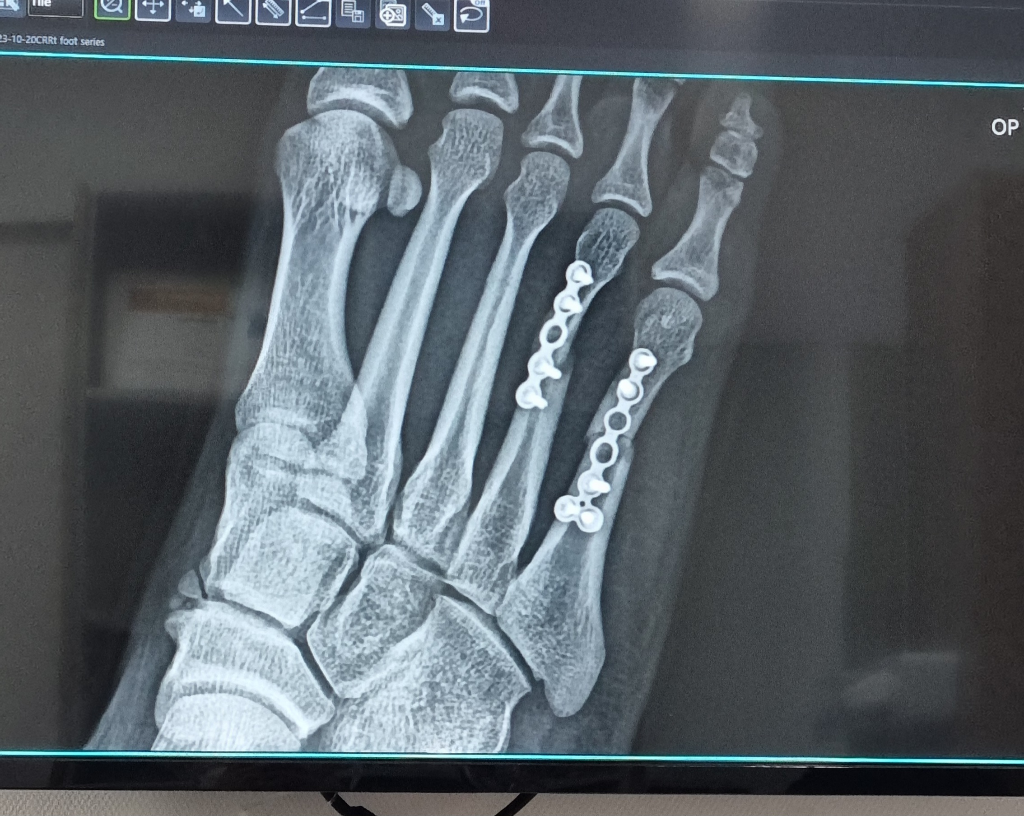

5중족골 3주차 엑스레이 질문드립니다

5중족골 골절로 수술을 받았고 지금 3주차에 엑스레이 찍고왔습니다.

3주차 엑스레이 사진보면 살짝 틀어져있는데

의사선생님 말씀으로 3주차 때 쯤에 원래 붙기전에는 틈새가 좀 넓어보일 수 있다고 걱정말라고하시는데

우선 수술직후의 엑스레이가 있다면 비교가 더 좋을 것 같습니다.

3주차의 경우라면 아직 유합여부를 판단하기는 힘들기 때문에 적어도 6주 까지는 체중부하를 최소화 하시면서 관찰을 하시는 것이 좋겠습니다.